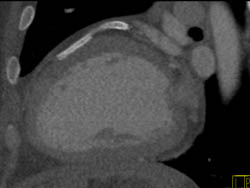

Dilated Reimplanted RCA in Ascending Aorta